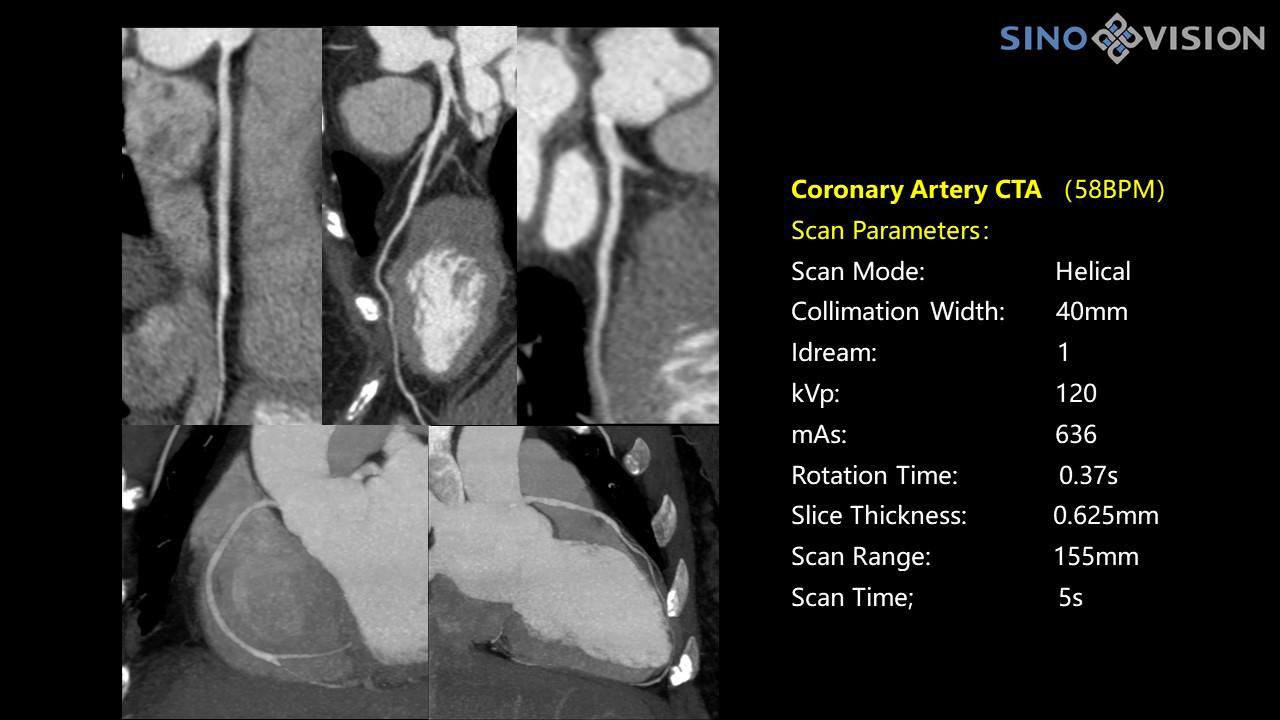

InsitumCT 768 является вершиной нового поколения широкоапертурных широкополосных компьютерных томографов. Этот КТ-сканер обеспечивает 128 срезов КТ при апертуре 76 см, увеличивая производительность визуализации до 21 л/см, способствуя точной диагностике и лечению заболеваний и значительно улучшая клинические характеристики и масштабируемость. Обеспечивает получение изображений высокого разрешения при низкой дозе облучения.

Компьютерный томограф Insitum CT 768 – старшая модель в линейке SinoVision Insitum. Еще более быстрый и еще более мощный, он значительно повышает пропускную способность кабинета КТ, обеспечивая при этом высококачественные исследования даже в самых сложных случаях практически во всех областях, включая кардиологию, исследования сосудистой системы, онкологию. Имеет специализированный педиатрический протокол исследования, минимализирующий лучевую нагрузку на ребенка.

Специализированная технология RTF позволяет уменьшать артефакты движения сердца, обеспечивая максимально точное клиническое изображение.

- Количество срезов: 128

- Толщина среза: 0.625 мм

Характеристики сканирования

- Минимальное время одного оборота рентгеновской трубки: От 0.37 до 2 сек

- Коронарный анализ

- Ретроспективный режим сканирования с ЭКГ-синхронизацией

- Проспективный режим сканирования с ЭКГ-синхронизацией

- Режим последовательного сканирования c ЭКГ-синхронизацией и без ЭКГ-синхронизации